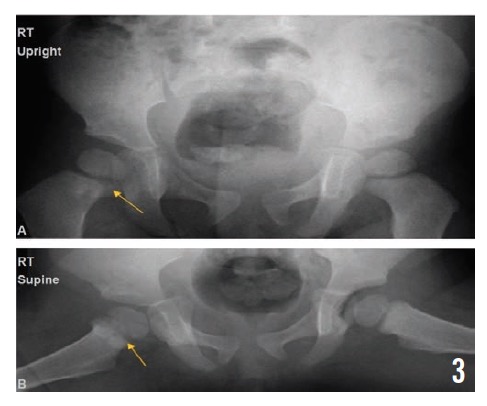

Radiographs of the pelvis at 2, 4, and 10 months (Figures 3, 4, and 5, respectively) showed healing osteomyelitis of the proximal right femur and changes that were concerning for early physeal closure at the right hip joint. Continued radiographic follow-up was suggested at that time.